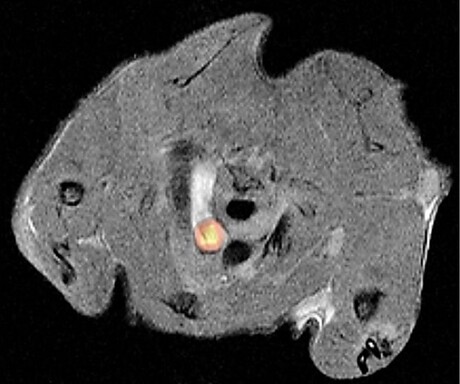

The new method for studying atherosclerosis is based on an artificial positron emission tomography (PET) reporter enzyme. This is specifically produced in mouse vascular muscle cells by a genetic trick. It causes the accumulation of a radioactive substance, the PET tracer, in these cells. The radioactive substance, which is harmless to the animal, is detected by PET and visualised on a screen.

PET is a clinically established method that is used, for example, to examine tumour patients. As a non-invasive technique, PET imaging puts less strain on the organism than many other examination procedures. By combining PET with magnetic resonance imaging (MRI), the research team is now able to track the position and number of vascular muscle cells in the body.

“This method allows us to observe in living animals how the labelled cells are involved in the development of atherosclerosis,” explained Dr Susanne Feil, first author on the study. For example, it is possible to see where vascular muscle cells accumulate in blood vessels and contribute to the development of plaques. By visualising such cell accumulations, conclusions can be drawn as to whether changes are harmless or could have life-threatening effects, for example because they could lead to vascular occlusions and infarcts.